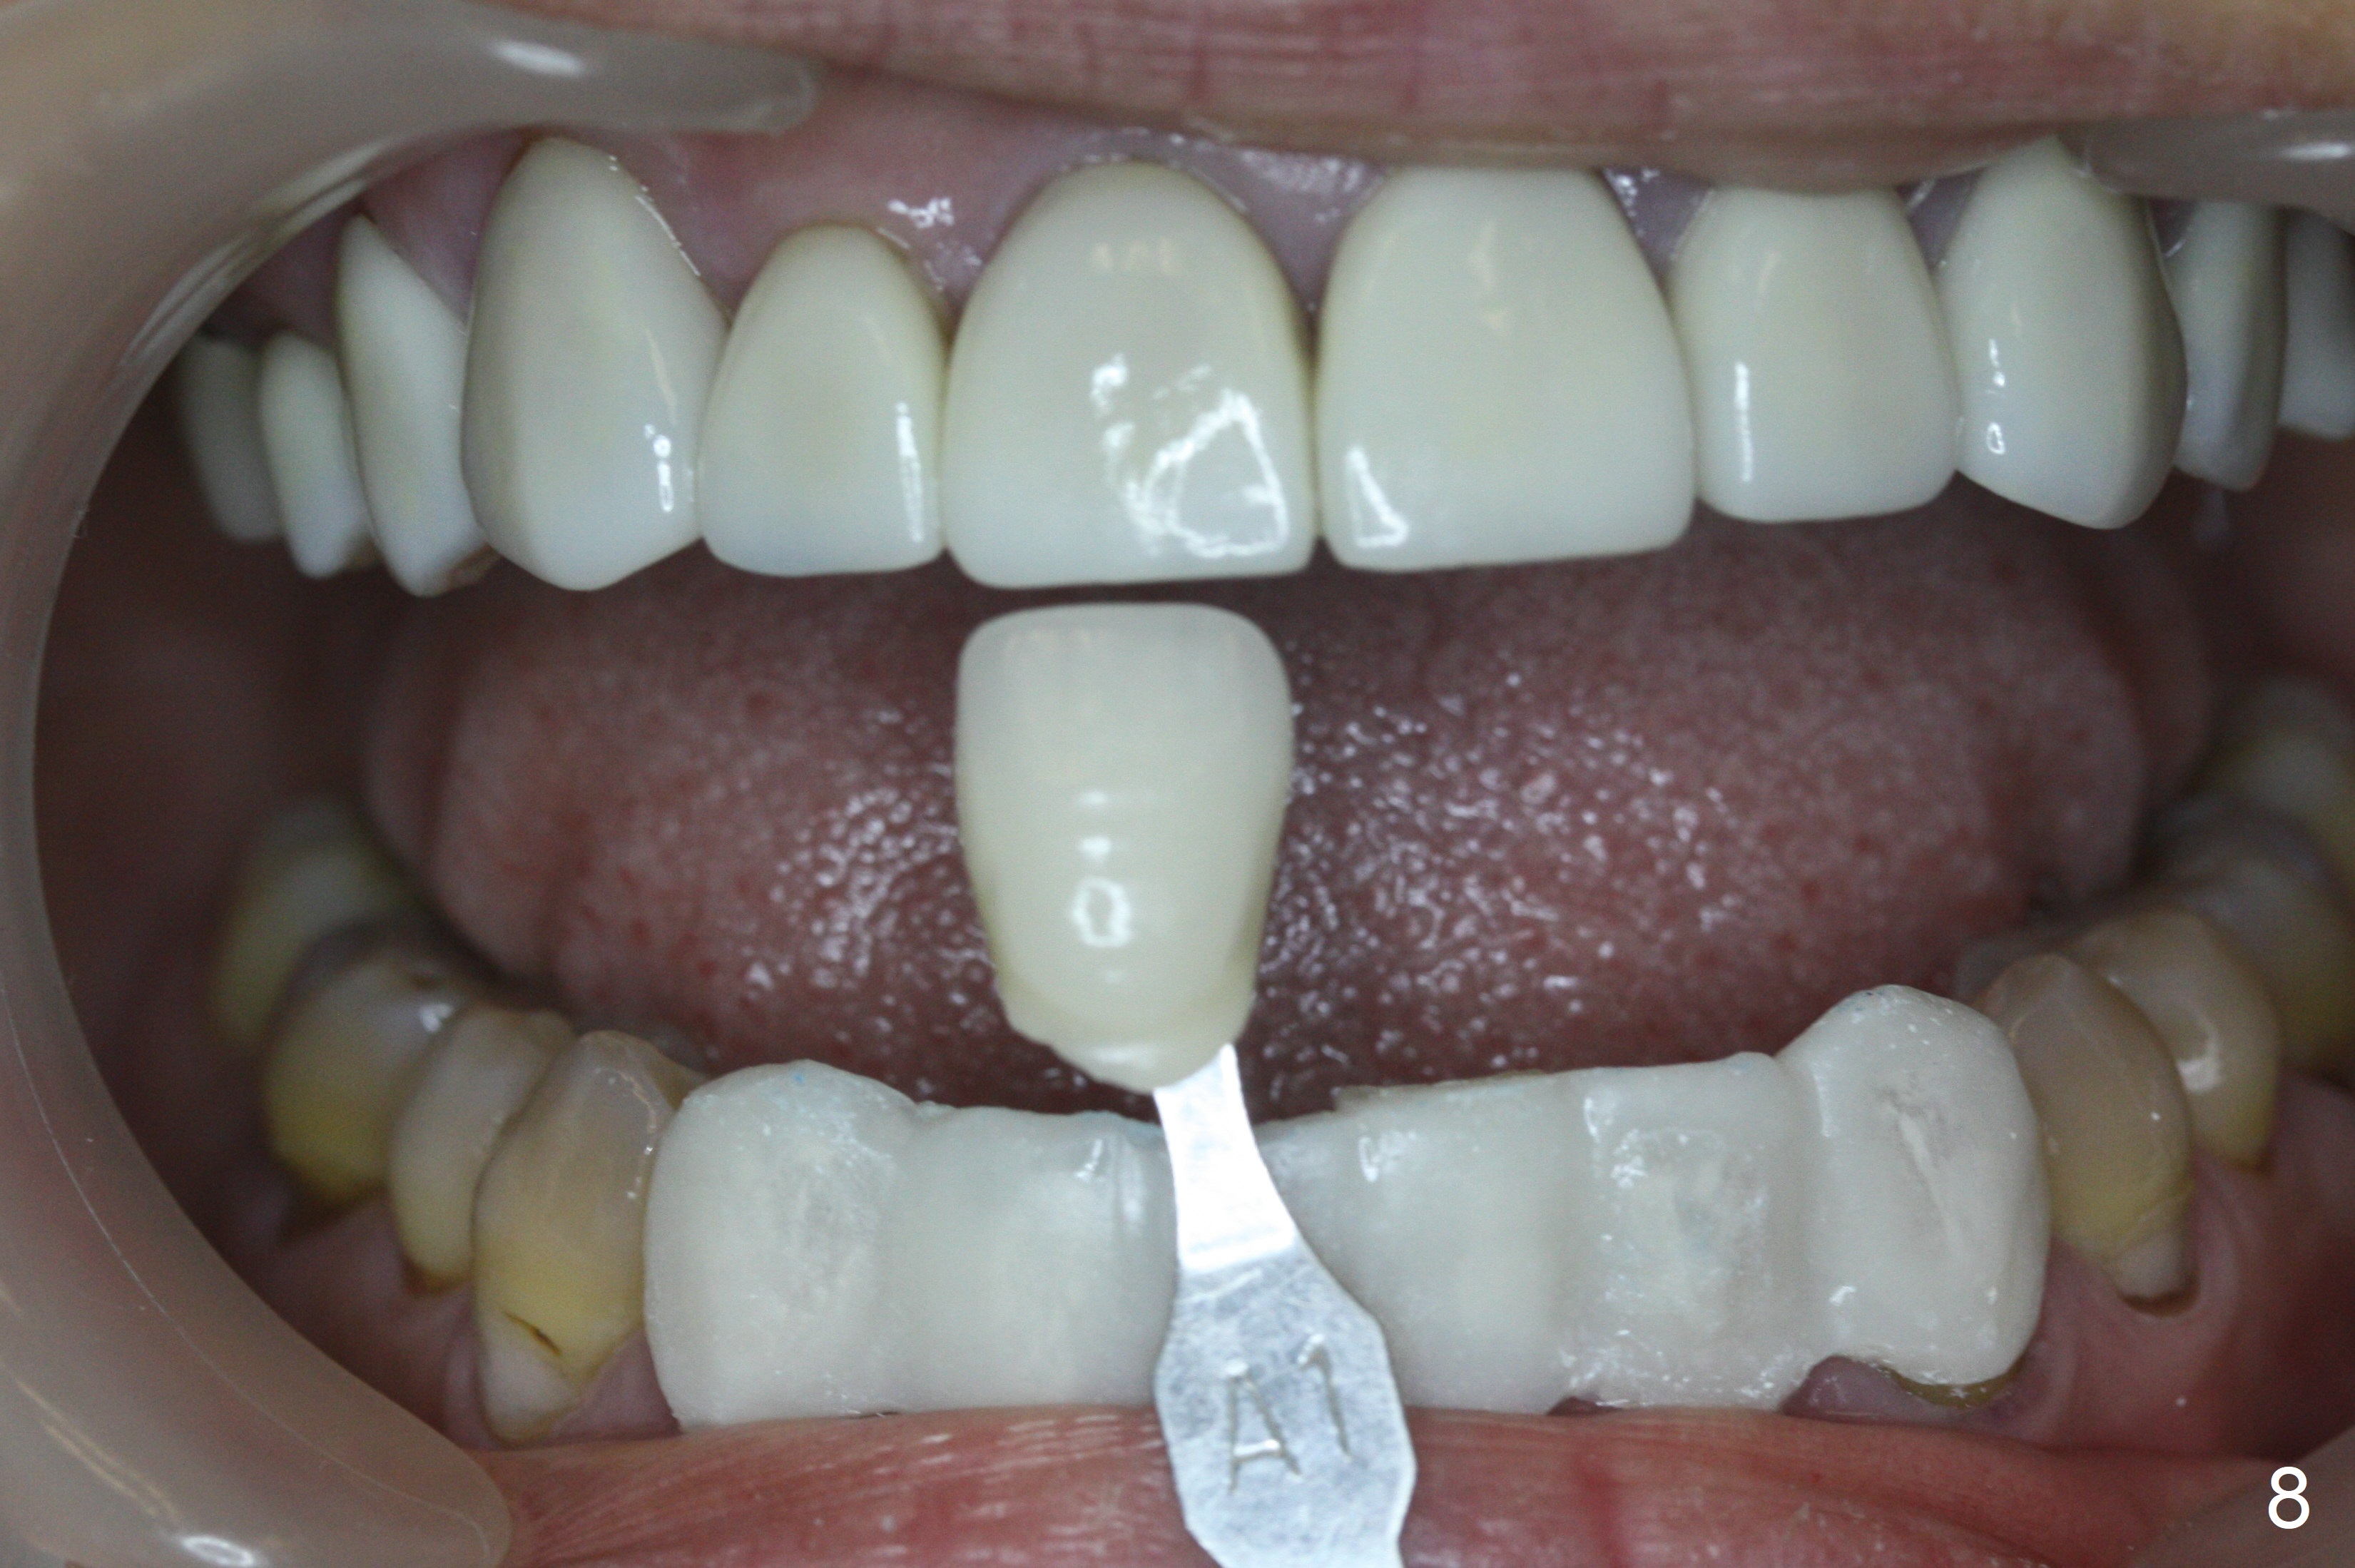

After prep (Fig.5), stump shade is chosen (Fig.6). Although B1 was selected for the upper veneers (Fig.7), the patient prefers to have A1 for the lower ones (Fig.8).